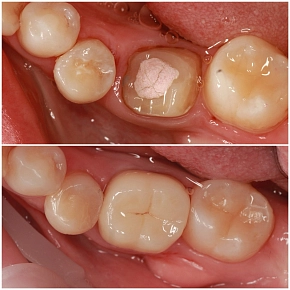

Клинический случай